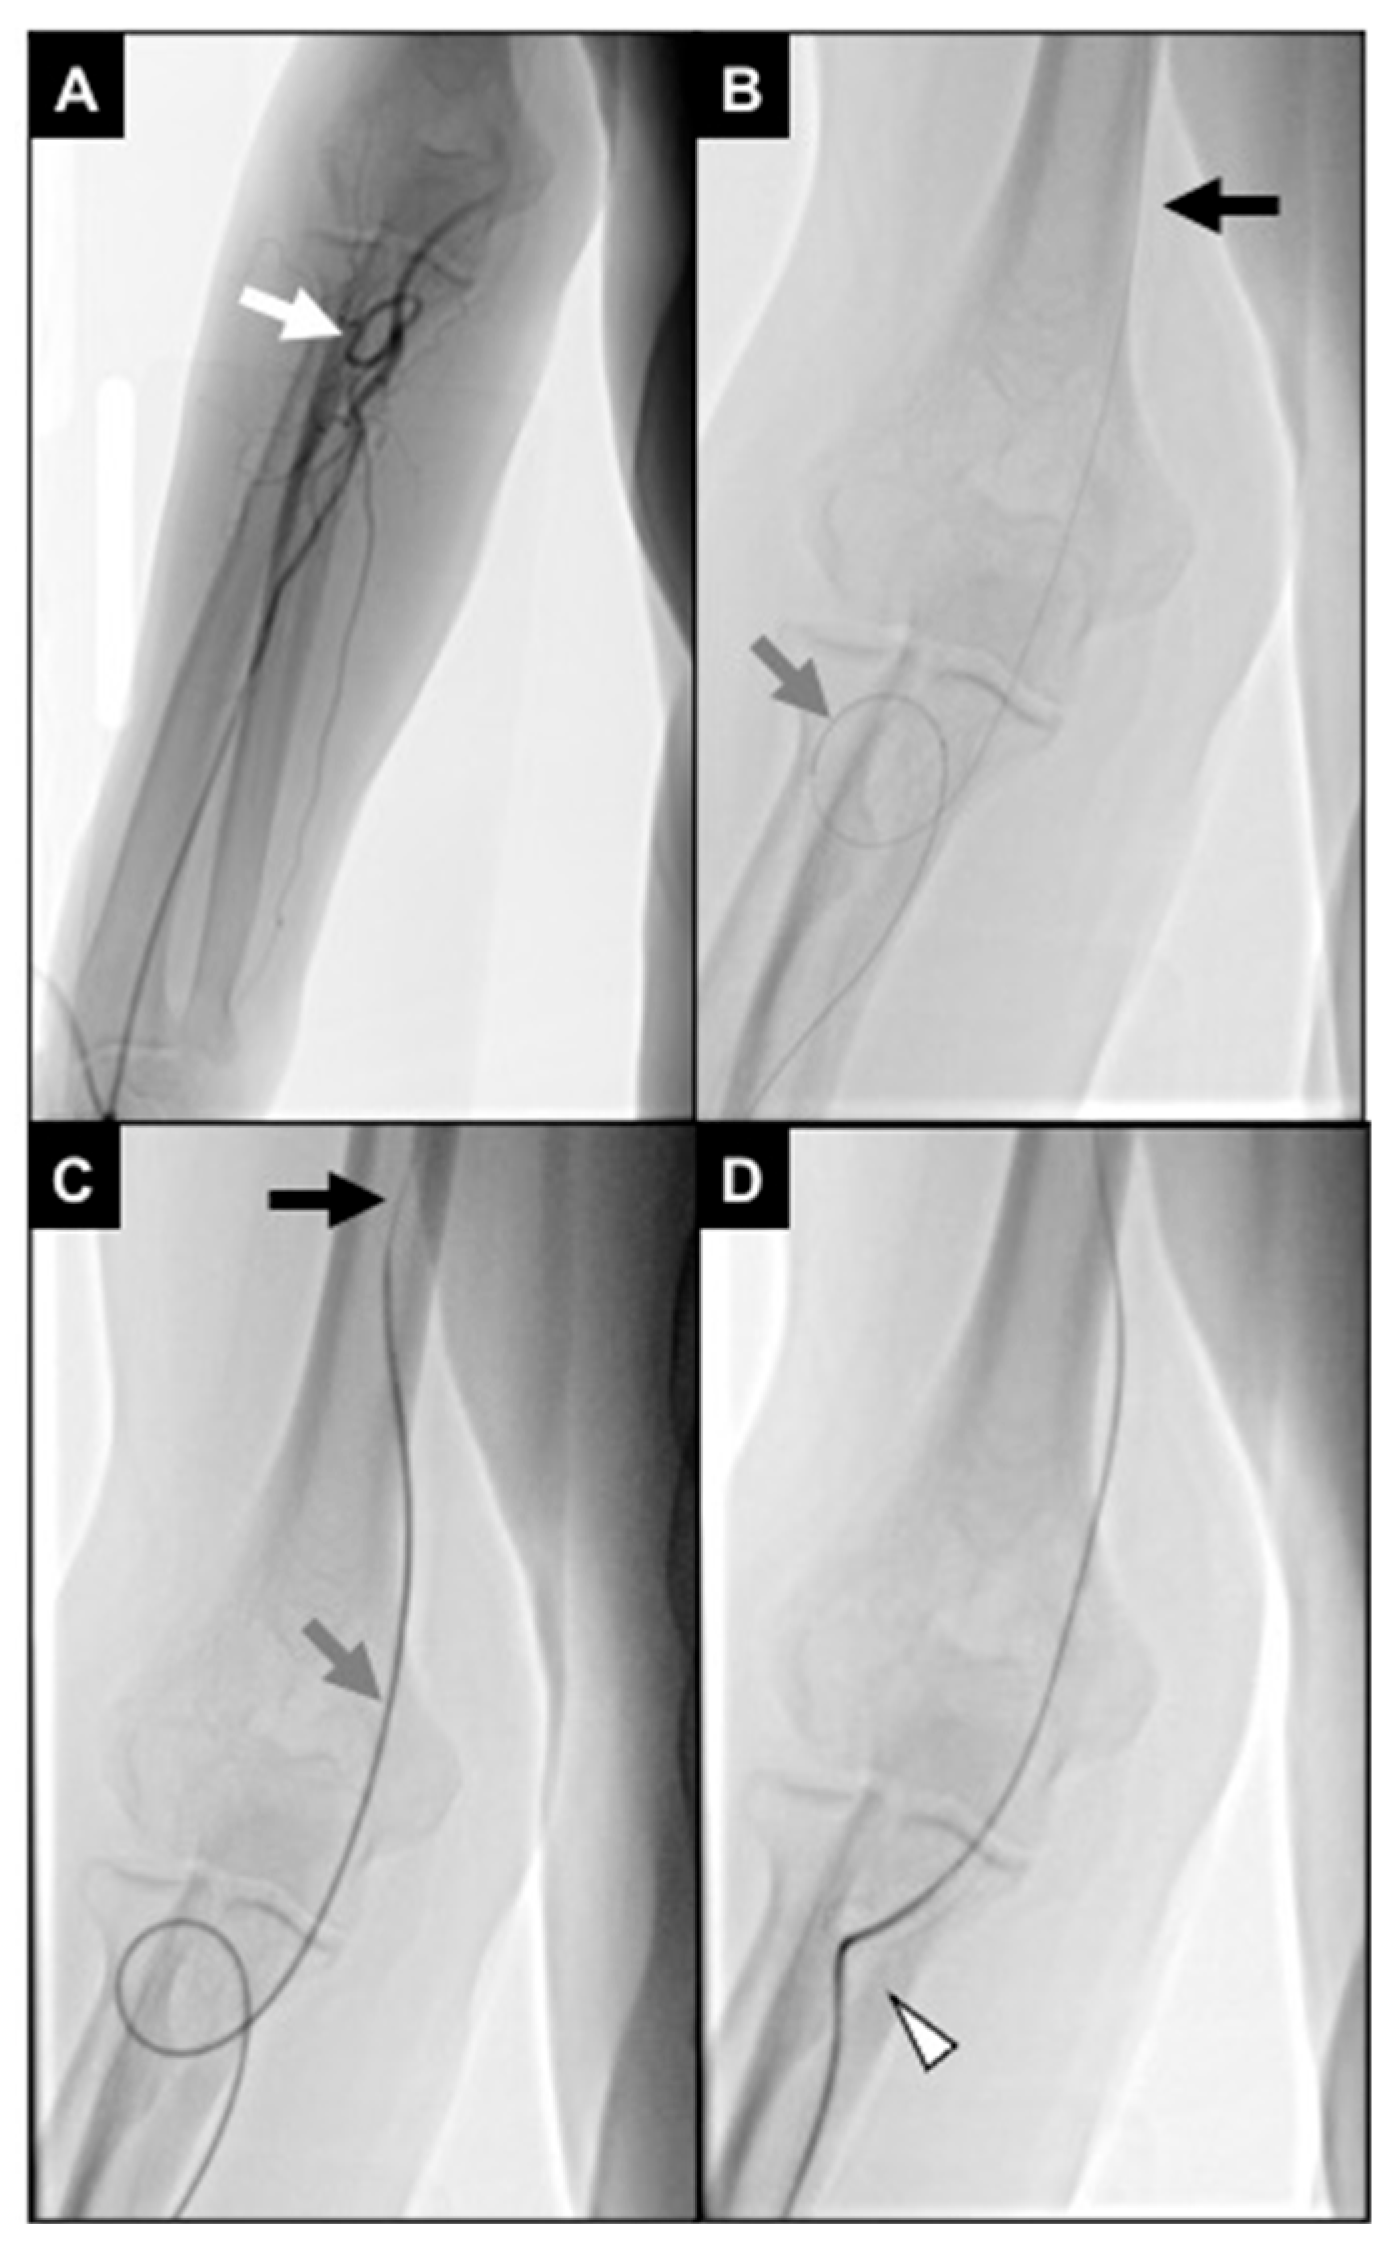

No statistical differences occurred in technical success rates (96.8% in group R and 100% in group L, p-value > 0.05). One patient in group R required crossover to right femoral access because of severe brachial artery coiling not allowing proper catheter handling (Figure 7).

Figure 7.

An 87-year-old man undergoing TACE for an HCC. (A) Initial fluoroscopic control showing distal brachial artery severe coiling (white arrow); (B) a 2.4Fr microcatheter (gray arrow) was navigated through the coiling, and a .018″ stiff guidewire (black arrow) was advanced up to the middle third of the brachial artery; (C) the microcatheter was exchanged with a 5Fr multipurpose diagnostic catheter (gray arrow), and a .035″ superstiff guidewire (black arrow) was adopted to loosen the coiling; during this maneuver, the patient referenced pain in the elbow; (D) brachial artery coiling was resolved; however, the vessel route remained angled (white arrowhead), not allowing proper catheter handling.